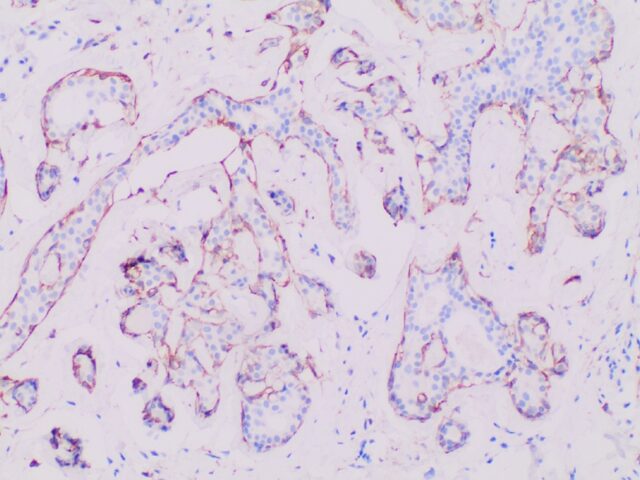

Immunohistochemistry (IHC)

Traditional pathology methods such as immunohistochemistry are the gold standard in characterizing tissue morphology and confirming target molecule expression. When combined with genetic, RNA transcript and protein information, they can be used to decipher the molecular pathways that correlate to an observed phenotype.